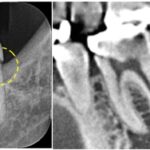

古い修復物の境目から虫歯が進行しており、レントゲン写真でも歯の神経に近接している状態でした。

歯髄検査の結果、歯髄は正常であることから、神経の保存は可能な状態でした。

また、虫歯の位置や歯列の位置からも、歯髄保存治療のアクセスが十分可能であることから、歯髄保存療法を実施することになりました。